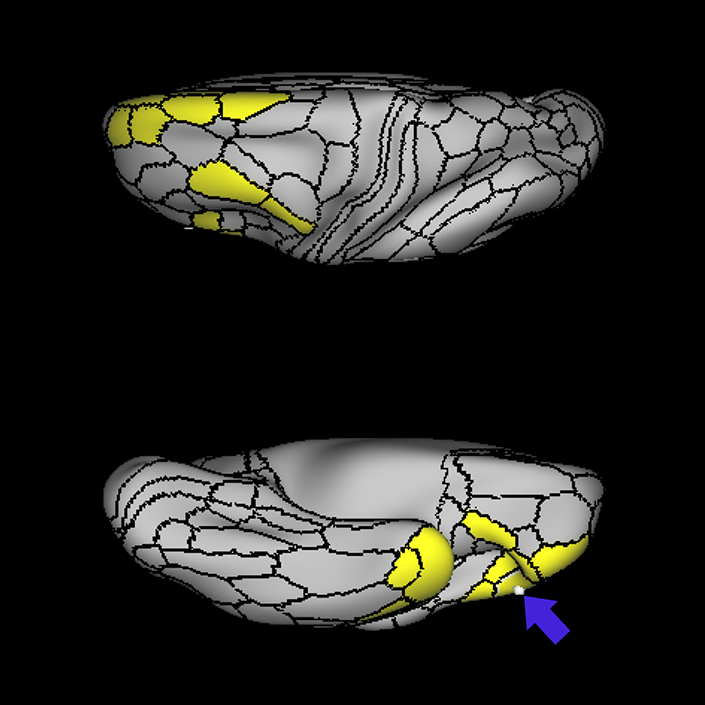

ᐅ SummaryArea PHT (parahippocampal temporal): part of the temporal lobe regions. Involved in processes related to the controlled retrieval of conceptual knowledge, while the anterior gyrus is involved in the automatic retrieval of specific semantic information. In contrast to the other areas of the lateral temporal cortex and temporal pole, that are all strongly associated with the task negative network, PHT is strongly associated with the task positive network. In addition, PHT (like TE1p anteriorly) is deactivated during language recognition tasks. ᐅ Where is it?Area PHT is found on the anterior portions of the subcentral gyrus (where the precentral and postcentral gyri meet just below the central sulcus). It involves the lateral surface of that operculum as well as the inferior surface which faces the Sylvian Fissure. ᐅ What are its borders?Area PHT borders area 6r anteriorly and OP4 posteriorly. Its superior border includes area 6v, as well as areas 4 and 3a. Its inferior borders include FOP1 and FOP2. ᐅ What are its functional connections?Area PHT demonstrates functional connectivity to areas IFSa, IFJa, IFJp, 6a,6ma, 6r, 46, 9-46d, p9-46v, p47r, FEF, PEF, SCEF, a24prime, p24prime, p32prime, 33prime, 23c, and 5mv in the frontal lobe, areas FOP1, FOP3, FOP4, FOP5, 43, PFcm, 52, MI, PoI1, and PoI2 in the insula opercular area, areas TE1p, TE2p and PHA3 in the temporal lobe, areas AIP, MIP, VIP, LIPv, LIPd, IPS1, IP0, IP1, IP2, PF, PFop, PFt, PGp, 7PC, 7pm, 7AL, 7PL, PCV and DVT in the parietal lobe, and areas V1, V2, FST, PH, TPOJ2 in the occipital lobe. ᐅ What are its white matter connections?Area PHT is structurally connected to the arcuate/SLF. Arcuate/SLF tracts wrap around the Sylvian fissure projecting toward the frontal lobe and turn medially to end at 44, IFJa, IFJp and IFSp. There are abundant posterior projections from the arcuate/SLF that terminate at the inferior parietal lobule at PGs, STV, PFm, PGi, TPOJ1 and TPOJ2. ᐅ What is known about its function?Area PHT lies in the posterior MTG leading into the angular gyrus. The posterior MTG is involved in processes related to the controlled retrieval of conceptual knowledge, while the anterior gyrus is involved in the automatic retrieval of specific semantic information. In contrast to the other parcellations of the lateral temporal cortex and temporal pole (TE1p, TE1m, TE1a, TE2p, TE2a, TGv, TGd, and TF) which are all strongly associated with the task negative network, PHT is strongly associated with the task positive network. In addition, PHT (like TE1p anteriorly) is deactivated during language recognition tasks. |

A: lateral-medial

B: anterior-posterior

C: superior-inferior

DTI image |